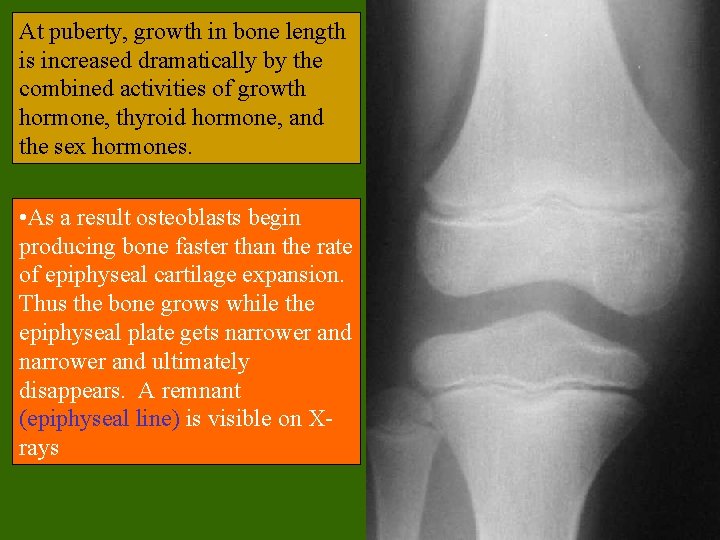

Growth in Bone Length • Epiphyseal cartilage (close to the epiphysis) of the epiphyseal plate divides to create more cartilage, while the diaphyseal cartilage (close to the diaphysis) of the epiphyseal plate is transformed into bone. This increases the length of the shaft.

At puberty, growth in bone length is increased dramatically by the combined activities of growth hormone, thyroid hormone, and the sex hormones. • As a result osteoblasts begin producing bone faster than the rate of epiphyseal cartilage expansion. Thus the bone grows while the epiphyseal plate gets narrower and ultimately disappears. A remnant (epiphyseal line) is visible on Xrays

Hormonal Effects on Bone • Growth hormone, produced by the pituitary gland, and thyroxine, produced by the thyroid gland, stimulate bone growth. – GH stimulates protein synthesis and cell growth throughout the body. – Thyroxine stimulates cell metabolism and increases the rate of osteoblast activity. – In proper balance, these hormones maintain normal activity of the epiphyseal plate (what would you consider normal activity? ) until roughly the time of puberty.

Hormonal Effects on Bone • At puberty, the rising levels of sex hormones (estrogens in females androgens in males) cause osteoblasts to produce bone faster than the epiphyseal cartilage can divide. This causes the characteristic growth spurt as well as the ultimate closure of the epiphyseal plate. • Estrogens cause faster closure of the epiphyseal growth plate than do androgens. • Estrogen also acts to stimulate osteoblast activity.